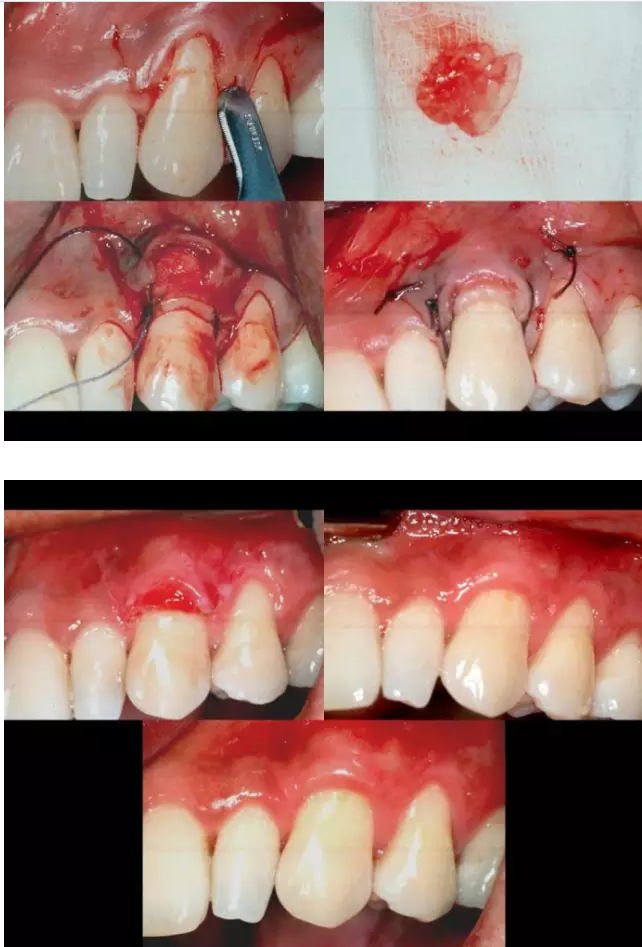

相關(guān)牙周防治